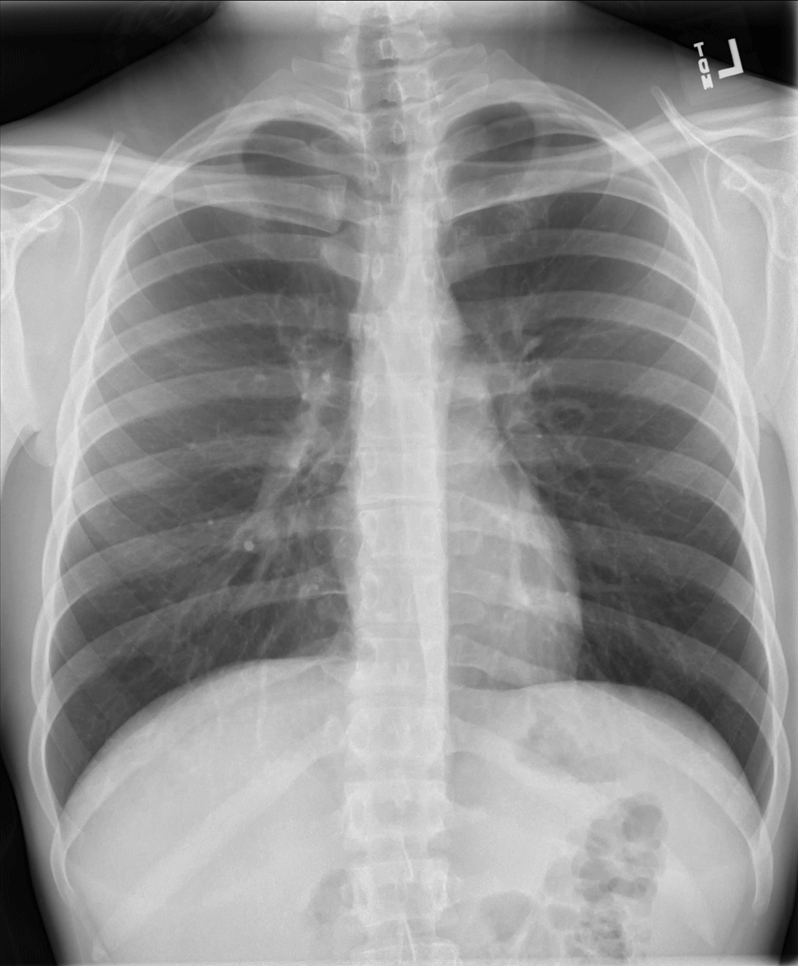

How To Tell If Chest X Ray Is Rotated . On ct however there is a cyst connected to the. Check if film is taken in full inspiration, with the diaphragm at the level of the 10th or 11th ribs posteriorly, and the 6th costal cartilage anteriorly. Rotation of a chest radiograph can simulate common pathological processes and make it hard to produce an appropriate diagnosis. If the patient is rotated to their right, then heart size may be underestimated. A small amount of patient rotation can lead to misinterpretation. Trachea, carina, bronchi and hilar. If the patient is rotated to their left, then the heart may appear enlarged. The pa view is used to investigate a plethora of. This patient is rotated to their left (right shoulder forwards and left shoulder backwards) the.

The pa view is used to investigate a plethora of. A small amount of patient rotation can lead to misinterpretation. Trachea, carina, bronchi and hilar. Check if film is taken in full inspiration, with the diaphragm at the level of the 10th or 11th ribs posteriorly, and the 6th costal cartilage anteriorly. This patient is rotated to their left (right shoulder forwards and left shoulder backwards) the. If the patient is rotated to their right, then heart size may be underestimated. Rotation of a chest radiograph can simulate common pathological processes and make it hard to produce an appropriate diagnosis. On ct however there is a cyst connected to the. If the patient is rotated to their left, then the heart may appear enlarged.